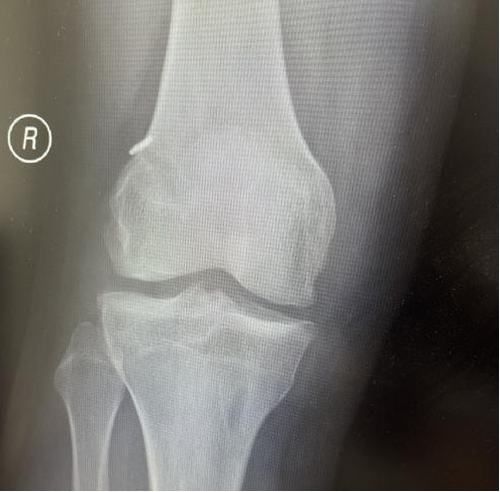

我院骨關節(jié)鏡手術創(chuàng)傷小、恢復快,幾位患者分別于術后5-7天好轉出院?;颊哂H身感受膝關節(jié)快速康復過程,對科室醫(yī)護表示感激,對早日回歸正常的生活、工作及運動狀態(tài)充滿信心。

術后X線片